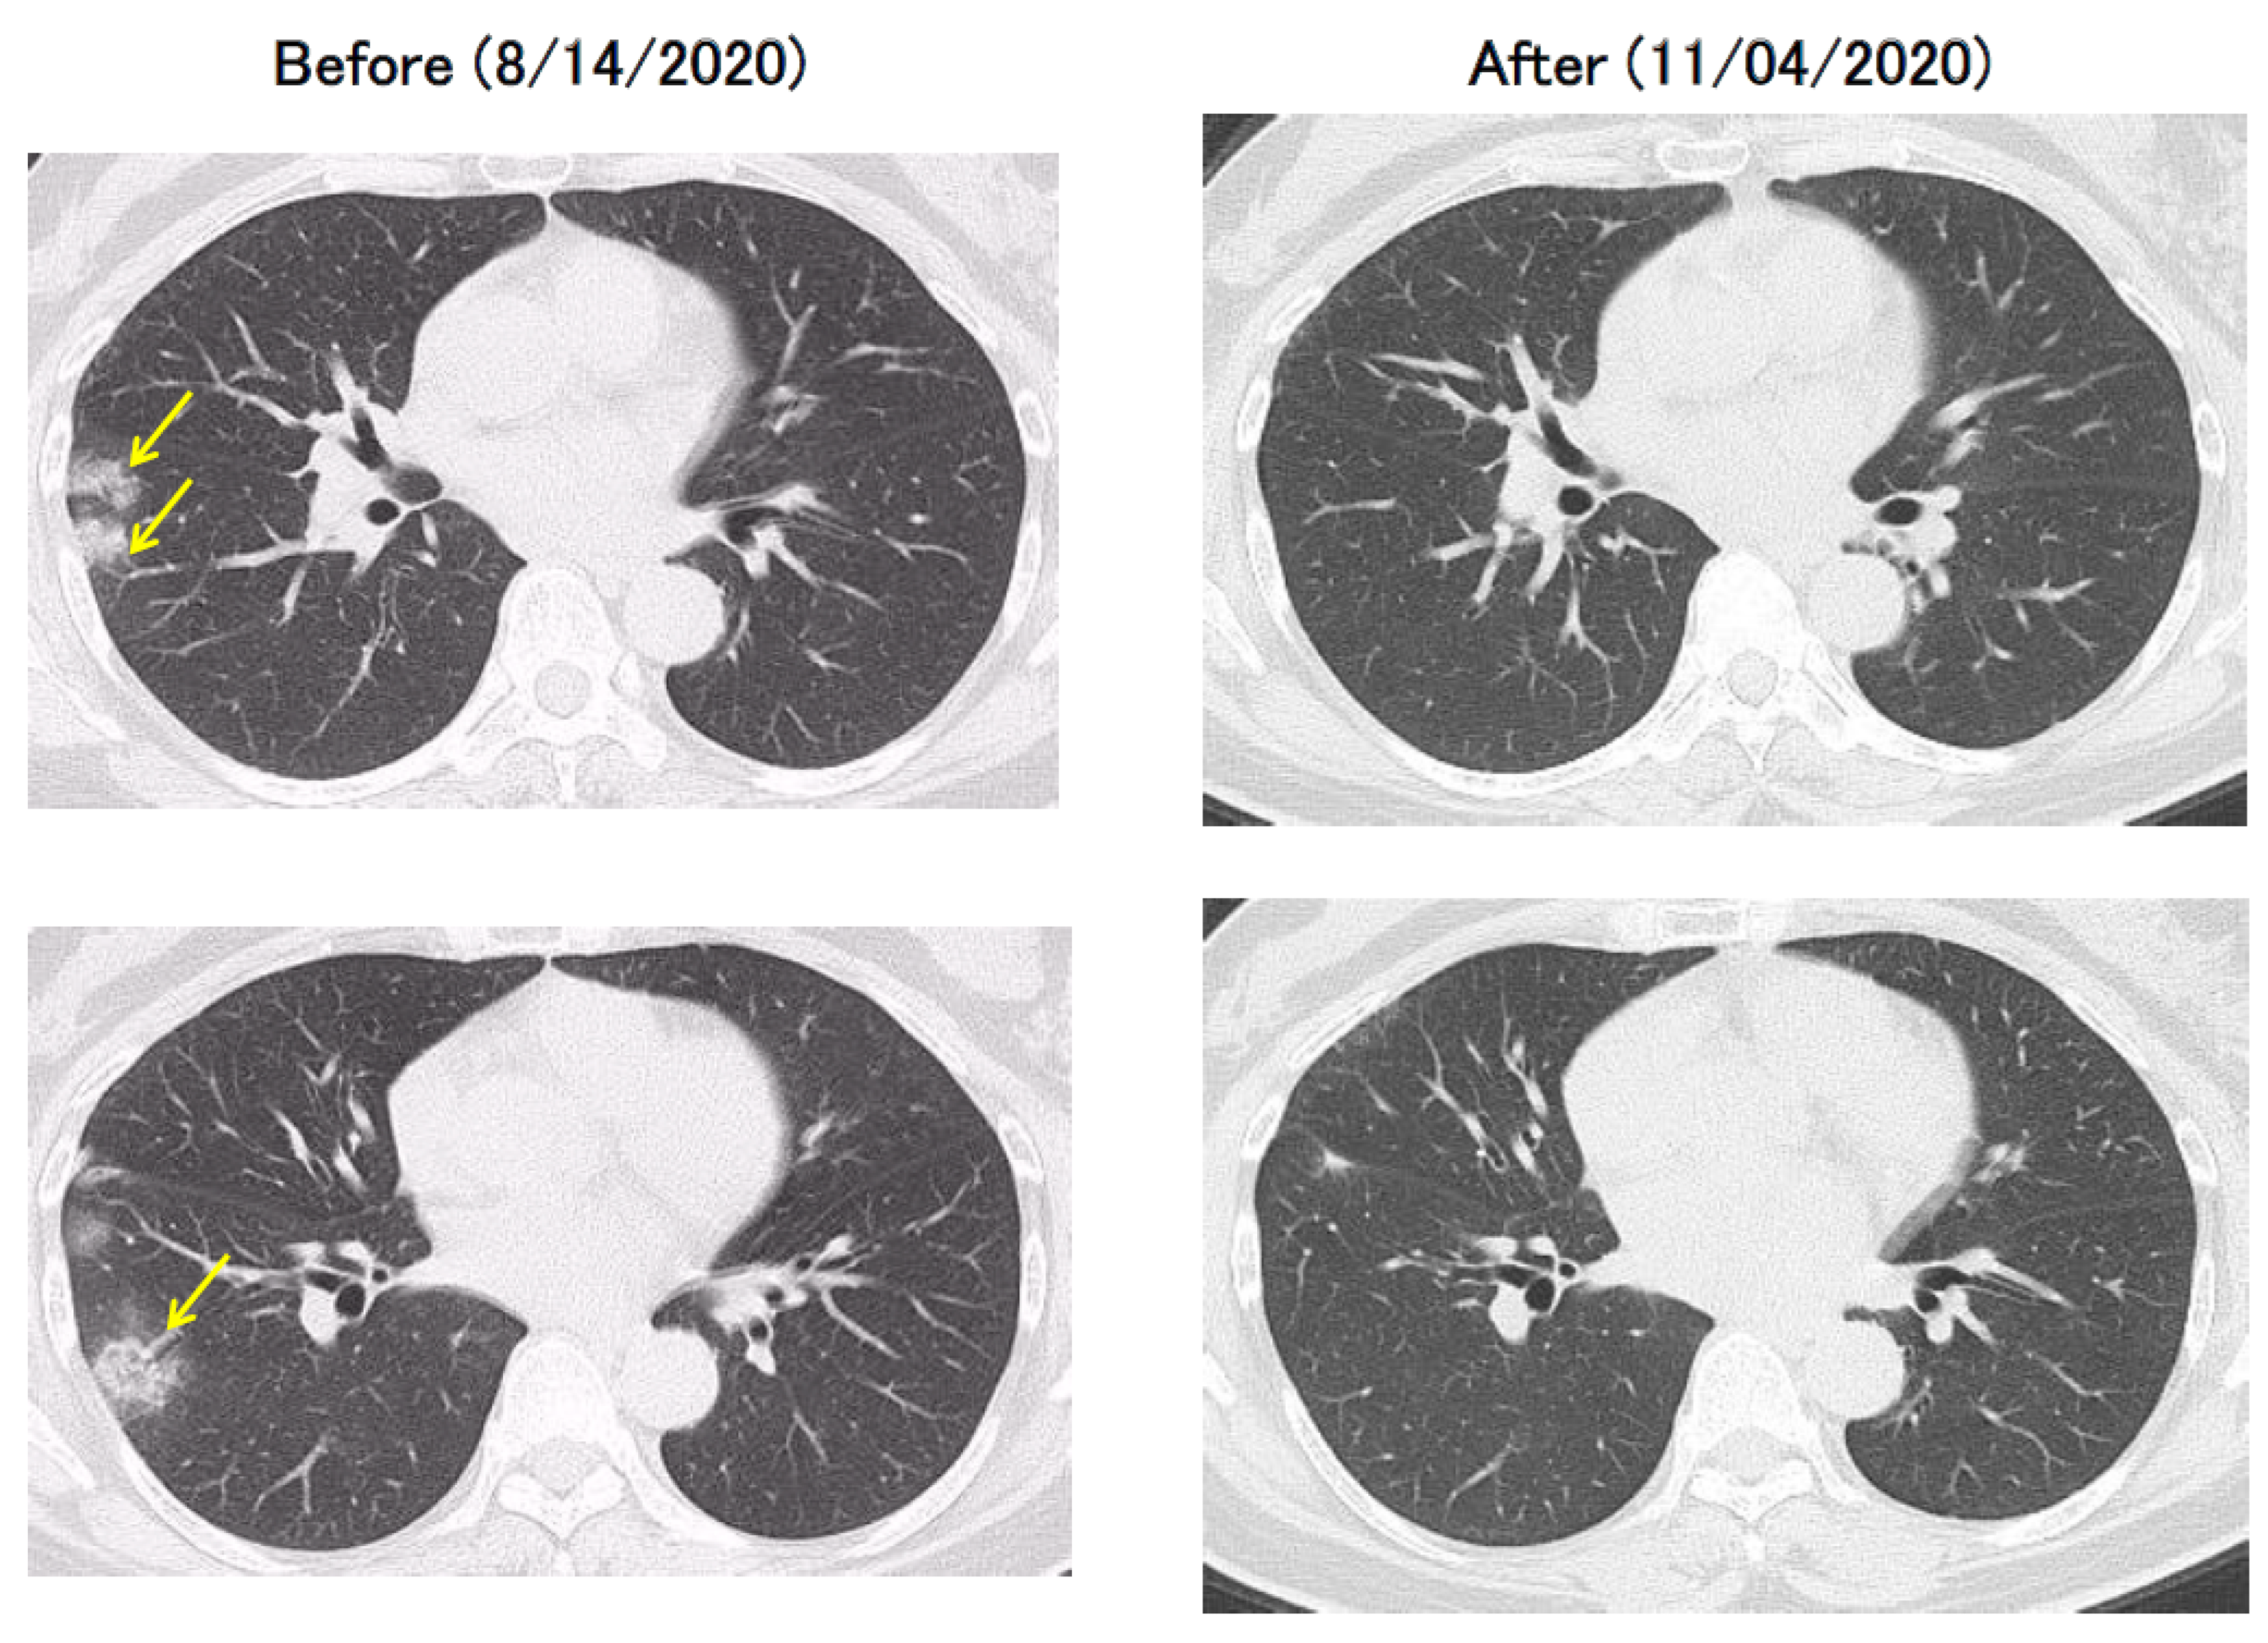

This case was clinically COVID-19 although repeated PCR test results were negative because the chest CT showed a clear image of pneumonia and a clear family history of infection was present (

Figure 3).

The patient was clinically thought to have COVID-19; however, as a definitive diagnosis could not be made through PCR testing, the patient was followed-up without hospitalization and without specific treatment, and at the 2-month follow-up, the pneumonia on the CT image disappeared (

Figure 3). This case is educational and demonstrates that false-negative PCR tests do occur.